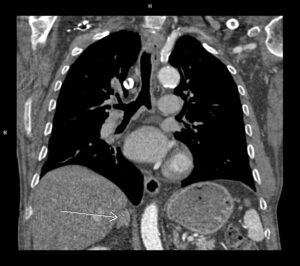

Discuţie caz nr 96: Boală Barlow este un sindrom clinic datorat prolapsului de valvă mitrală; se evidențiază deplasarea în sistolă a cuspelor mitrale spre atriul stâng ce asociază disjuncţie de inel mitral și fenomen de curbare posterioară. Această forțare a miocardului ventricular stâng din segmentele laterale poate duce la apariția de arii de fibroză că substrat aritmogen – materializate sub formă de priză de contrast (nu e cazul la acest pacient).